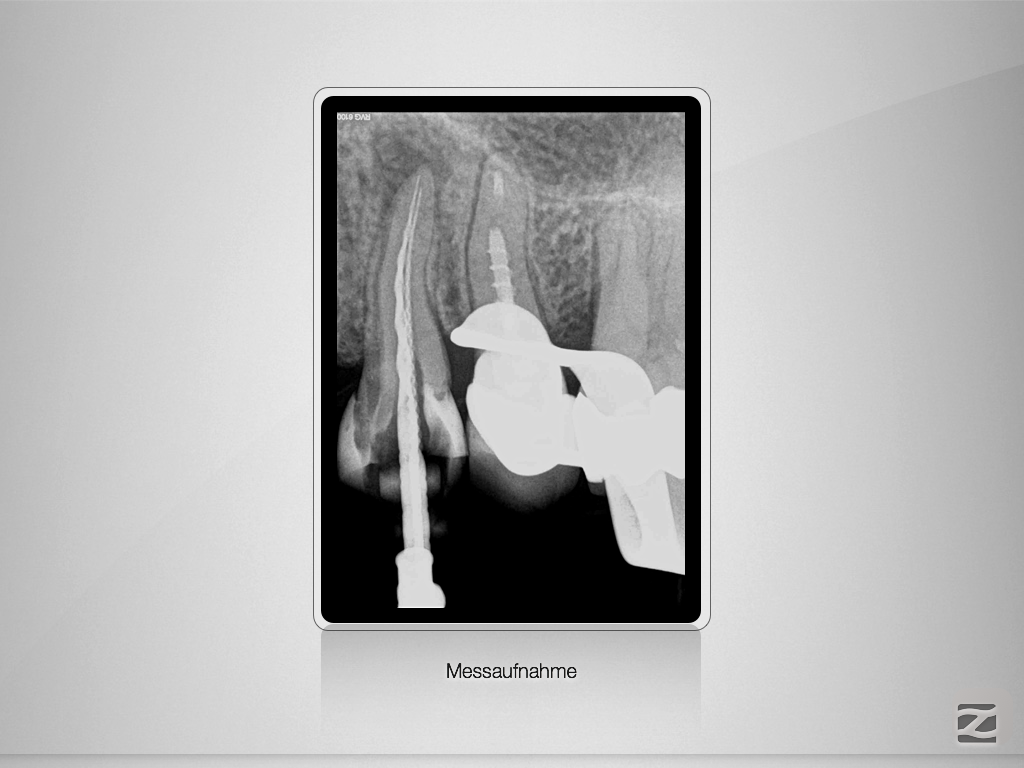

Gib mir ein „H“